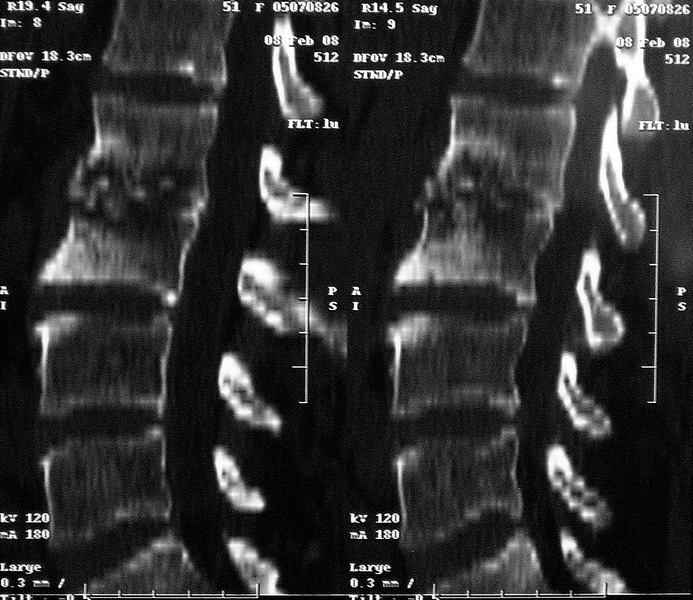

Коваленко А.Н. 12 Февраль 2008, 22:13

MRI через три недели

По данным представленных КТ и МРТ у больной имеется достаточно выраженная степень деструкции тел позвонков (около 30% общей костной массы тела позвонка), что определяет высокий риск возникновения патогических переломов и появления локальной кифотической деформации на этом уровне.

Судя по снимкам похоже идет речь о спинальном остеомиелите для диф диагноза стоит провести черезкожную пункционную биопсию(с помощью КТ)

Уважаемый доктор! судя по последнему МРТ процесс затрагивает соседние позвонки с переходом процесса через диск. Для туберкулёза как раз и характерна картинка "целующихся" позвонков. При бактериальном процессе диск страдает лишь вторично. Туберкулиновые пробы могут быть в пределах нормы, лёгкие - чистые. Вообще туберкулёз последнее время стал очень коварен и атипичен. Такие случаи отмечались у детей старшего возраста.